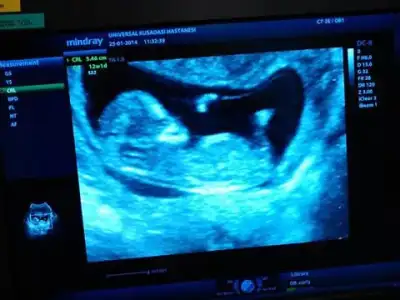

zeynepcim 12 haftalık bu resimde bebişim bu cuma 16 olcaz 7 yaşında kızım var kızları çok sevsemde bu farklı olsun istiyo insan benim resmide face ye koyarmısın birde face adınız ne bende bakayım $1624209_10202220567127945_1171059103_n.webp

12 haftalık bebebiğim..ben birsey anlayamadım.kız yada erkek bir tahmini olan var mı..

12 KB · Görüntüleme: 92

$IMG_2633.webp merhaba kızlar 13+3 haftalık cinsiyeti çok merak konusu:44: evimizde ilk bebeğimiz allah biliyor ya gönlüm hep kızdan yana sağlıklı sihatli olsun en öncelik o tabi takipteyim lütfenn benimkinde ne görünüyor dr söylemedi :50:

Kiza benziyo canim ama nubu net goremedn soyluyorum bi ihtimal

Farklı bir ultrason koymuştum ama fatoş arkadaşta ikiliem de kalmıştı, cinsiyet namında tahmin zordu biraz, hem kıza hem erkeğe benziyor demişti bu resim daha net, doktor da %85 kız demişti bu arada.. :emir_bebek::16: